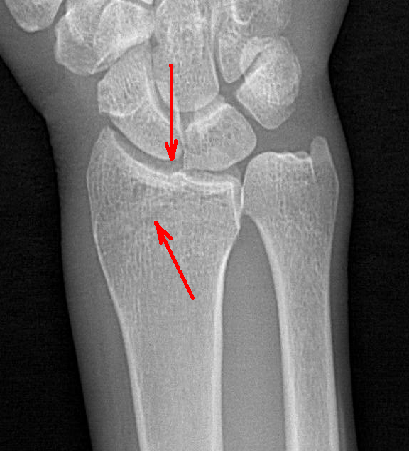

隱匿性骨折高清圖像

其次,動態(tài)DR 空間分辨率高,圖像清晰,診斷準(zhǔn)確率高,且具有視頻保存、回放功能,可以完整的記錄整個透視動態(tài)圖像,便于重復(fù)觀察、分析,減少遺漏。相對于傳統(tǒng) X 線檢查,動態(tài)DR輻射量較小,可有效減少 X 線所造成的輻射,呵護(hù)醫(yī)患健康。

普利德多功能動態(tài)DR將數(shù)字?jǐn)z影、數(shù)字透視、數(shù)字造影、毫秒級高清點片、影像實時保存與回放、全景拼接等多種功能集于一身。像素尺寸達(dá)到業(yè)界領(lǐng)先的100微米,率先實現(xiàn)5.0lp/mm超高分辨率成像,大幅提升細(xì)節(jié)檢測能力;透視幀率高達(dá)30幀/秒,有效避免漏診、誤診;靜態(tài)攝影有效像素高達(dá)1800萬,較之于傳統(tǒng)900萬點片像素,圖像細(xì)節(jié)更加清晰銳利,影像質(zhì)量躍升至新高度,為隱匿性肋骨骨折診斷提供至清影像,輔助醫(yī)生實現(xiàn)精準(zhǔn)診療!